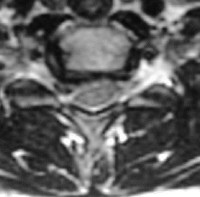

Hernie Discale

Hernie discale "molle"

postérolatérale droite

Coupe IRM

Une hernie discale cervicale qui siège à l’arrière du disque peut aggraver la situation et comprimer soit le nerf sortant entre les deux vertèbres (la racine nerveuse) ou même si la hernie est plus volumineuse, comprimer l’ensemble de la moelle épinière qui passe derrière le disque.